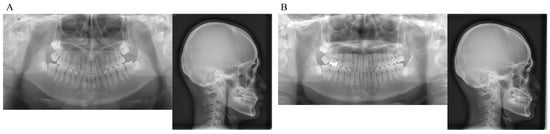

Figure 9. Panoramic radiographs and lateral cephalograms. (A) At termination of active treatment (age, 17 years 9 months). (B) At completion of eruption of the maxillary left third molar (age, 21 years 3 months).

Panoramic radiographs showed good root parallelism, no root resorption in the tractioned maxillary left canine or other teeth, and no abnormalities in the periodontal tissue. The maxillary left third molar, which had been impacted when active treatment was terminated, fully erupted 3 years and 6 months after active treatment was terminated. The maxillary right third molar and mandibular right and left third molars are impacted and scheduled for extraction (Figure 9).

Lateral cephalometric radiography showed the following changes in the anteroposterior position of the maxillary first molars before and after the use of the Hyrax-type expander: A′-Ms from 32.5 mm to 33.0 mm for the right and from 28.0 mm to 33.0 mm for the left, and ptm′-Ms from 18.5 mm to 19.0 mm for the right and from 23.0 mm to 19.0 mm for the right. Thus, the right first molar showed no change in position while the left first molar was moved distally by about 4.5 mm to almost the same position as the right one. The axial inclination angle of the right maxillary first molar was unchanged from 83.0° while that of the left first molar decreased from 88.0° to 83.0°, indicating that the mesially inclined left first molar was caused to slightly incline distally (Figure 10 and Table 1).

When active treatment was terminated, SNA was increased by 0.5° compared with before active treatment was terminated due to anterior maxillary growth. Although point B was retracted, the SNB was unchanged at 88.5° due to anterior mandibular growth, which resulted in a 0.5° increase in ANB. Vertically, FMA was increased by 0.5°, indicating a slight clockwise rotation of the mandible. U-1 to NA increased to 4.0 mm/22.5°, indicating labial tipping movement of the maxillary central incisor, while the L-1 to NB increased to 4.0 mm/20.5°and the FMIA decreased from 80.5° to 73.5°, indicating labial tipping of the mandibular central incisor. This resulted in the improvement of the interincisal angle to 135.5° (Figure 11 and Table 1).

At completion of eruption of the maxillary left third molar, there was a slight skeletal change (ANB: 0.5° decrease; FMA: 0.5° decrease) from the termination of active treatment, but there was no change in the position of the maxillary and mandibular anterior teeth and the maxillary first molar (Figure 12 and Table 1).